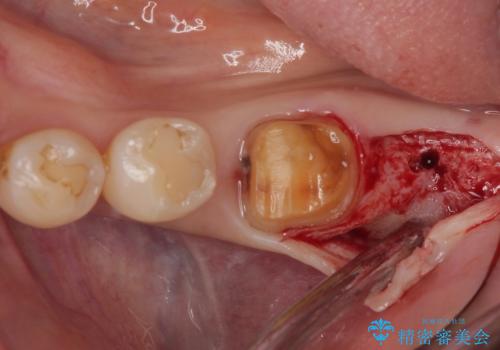

最後方歯は歯槽骨よりも深い部分にまでむし歯が及んでおり、患者様と相談の上、インプラントによる補綴治療を行うこととしました。

根尖部の病変が小さいことから抜歯即時埋入が選択されるところですが、抜歯窩洞が大きくなることと、窩洞直下に神経や血管が走行していることから、抜歯してから2,3ヶ月待機してから埋入することとしました。

手前の歯は、適合の悪いクラウンを最後方歯と同時にオールセラミッククラウンにて補綴治療を行うこととしました。